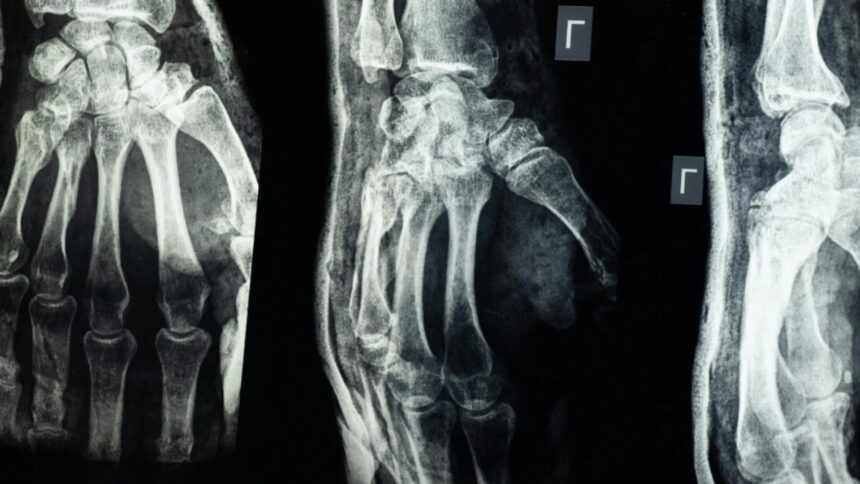

O echipă de cercetători din provincia Zhejiang, China, a creat un adeziv medical, denumit „Bone-02”, capabil să repare fracturile osoase în 2-3 minute. Acesta are potențialul de a înlocui implanturile metalice și de a reduce perioada de recuperare a pacienților.

Testele pe peste 150 de pacienți au arătat că „Bone-02” oferă o rezistență similară cu implanturile metalice, având o forță de lipire de peste 400 de livre și o rezistență la compresiune de aproximativ 10 MPa.